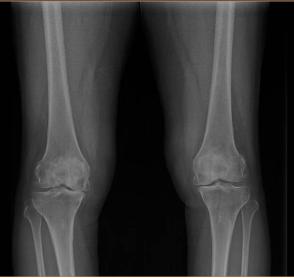

结果诊断为“左膝骨关节炎”。

刘宁主任指出,膝骨关节炎的根本原因是:关节软骨磨损与剥脱。随着年龄的增长及各种损伤,关节软骨会逐渐退变,磨损程度逐渐加重。软骨一旦磨损后很难再生,失去软骨的保护,走路时骨头磨骨头。骨头最外面的骨膜及周围的滑膜上神经丰富,关节痛感便会袭来。

膝关节炎是一种以退行性病理改变为基础的疾患。多患于中老年人群,其症状多表现为膝盖红肿痛、上下楼梯痛、坐起立行时膝部酸痛不适等。